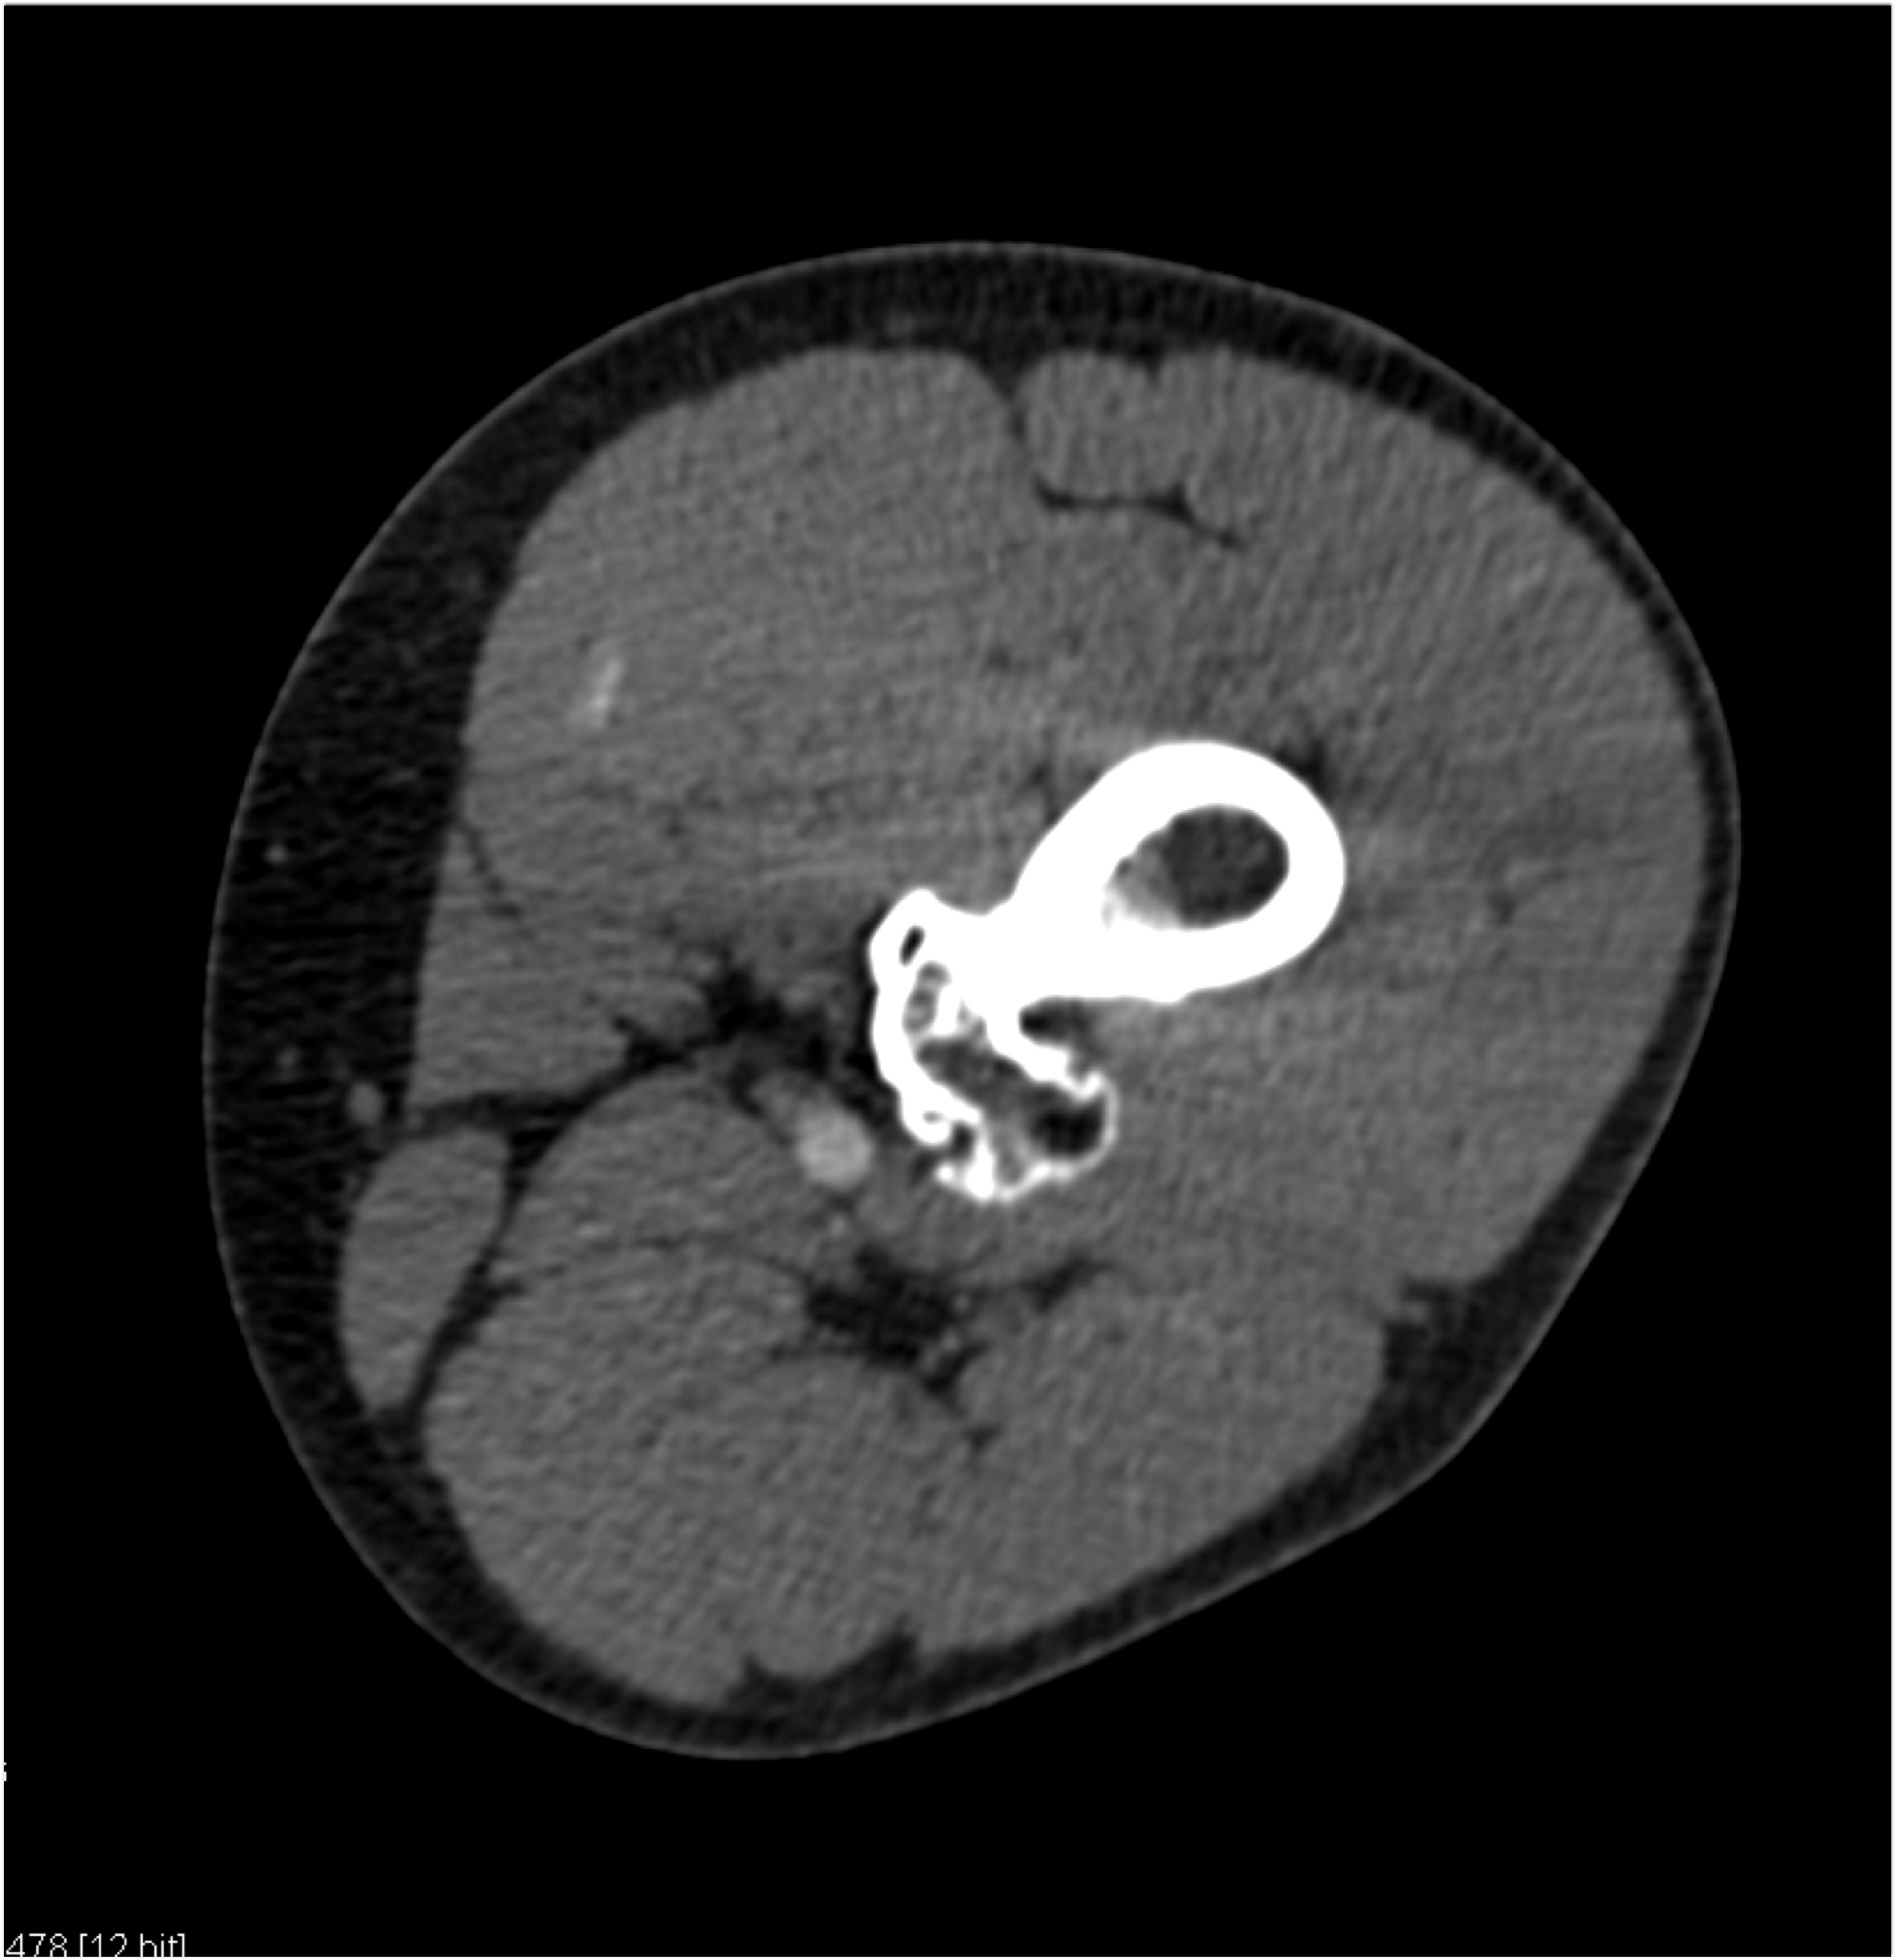

2) In this patient on dialysis for ESRD the best diagnosis is?

normal bypass graft

AV fistulae with aneurysms

vasculitis

infectious vascular disease